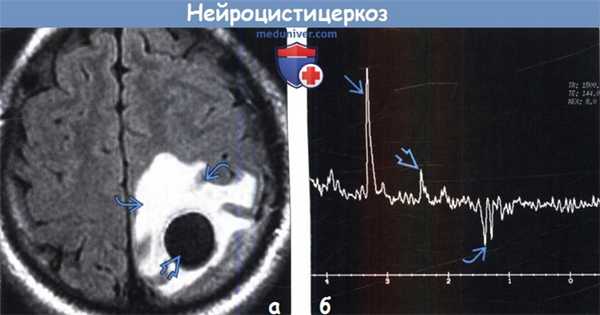

(а) МРТ, FLAIR, аксиальный срез: у пациента с НЦЦ определяется крупная киста ликворной интенсивности сигнала с обширным перифокальным вазогенным отеком. В коллоидно-везикулярной стадии НЦЦ начинается процесс дегенерации личинки, что вызывает острую воспалительную реакцию и обусловливает развитие выраженного перифокального отека.

(б) МР-спектроскопия полости кисты, TR1500, ТЕ 144: пики холина (3,2 ppm), сукцината (2,4 ppm) и лактата (1,3 ppm).